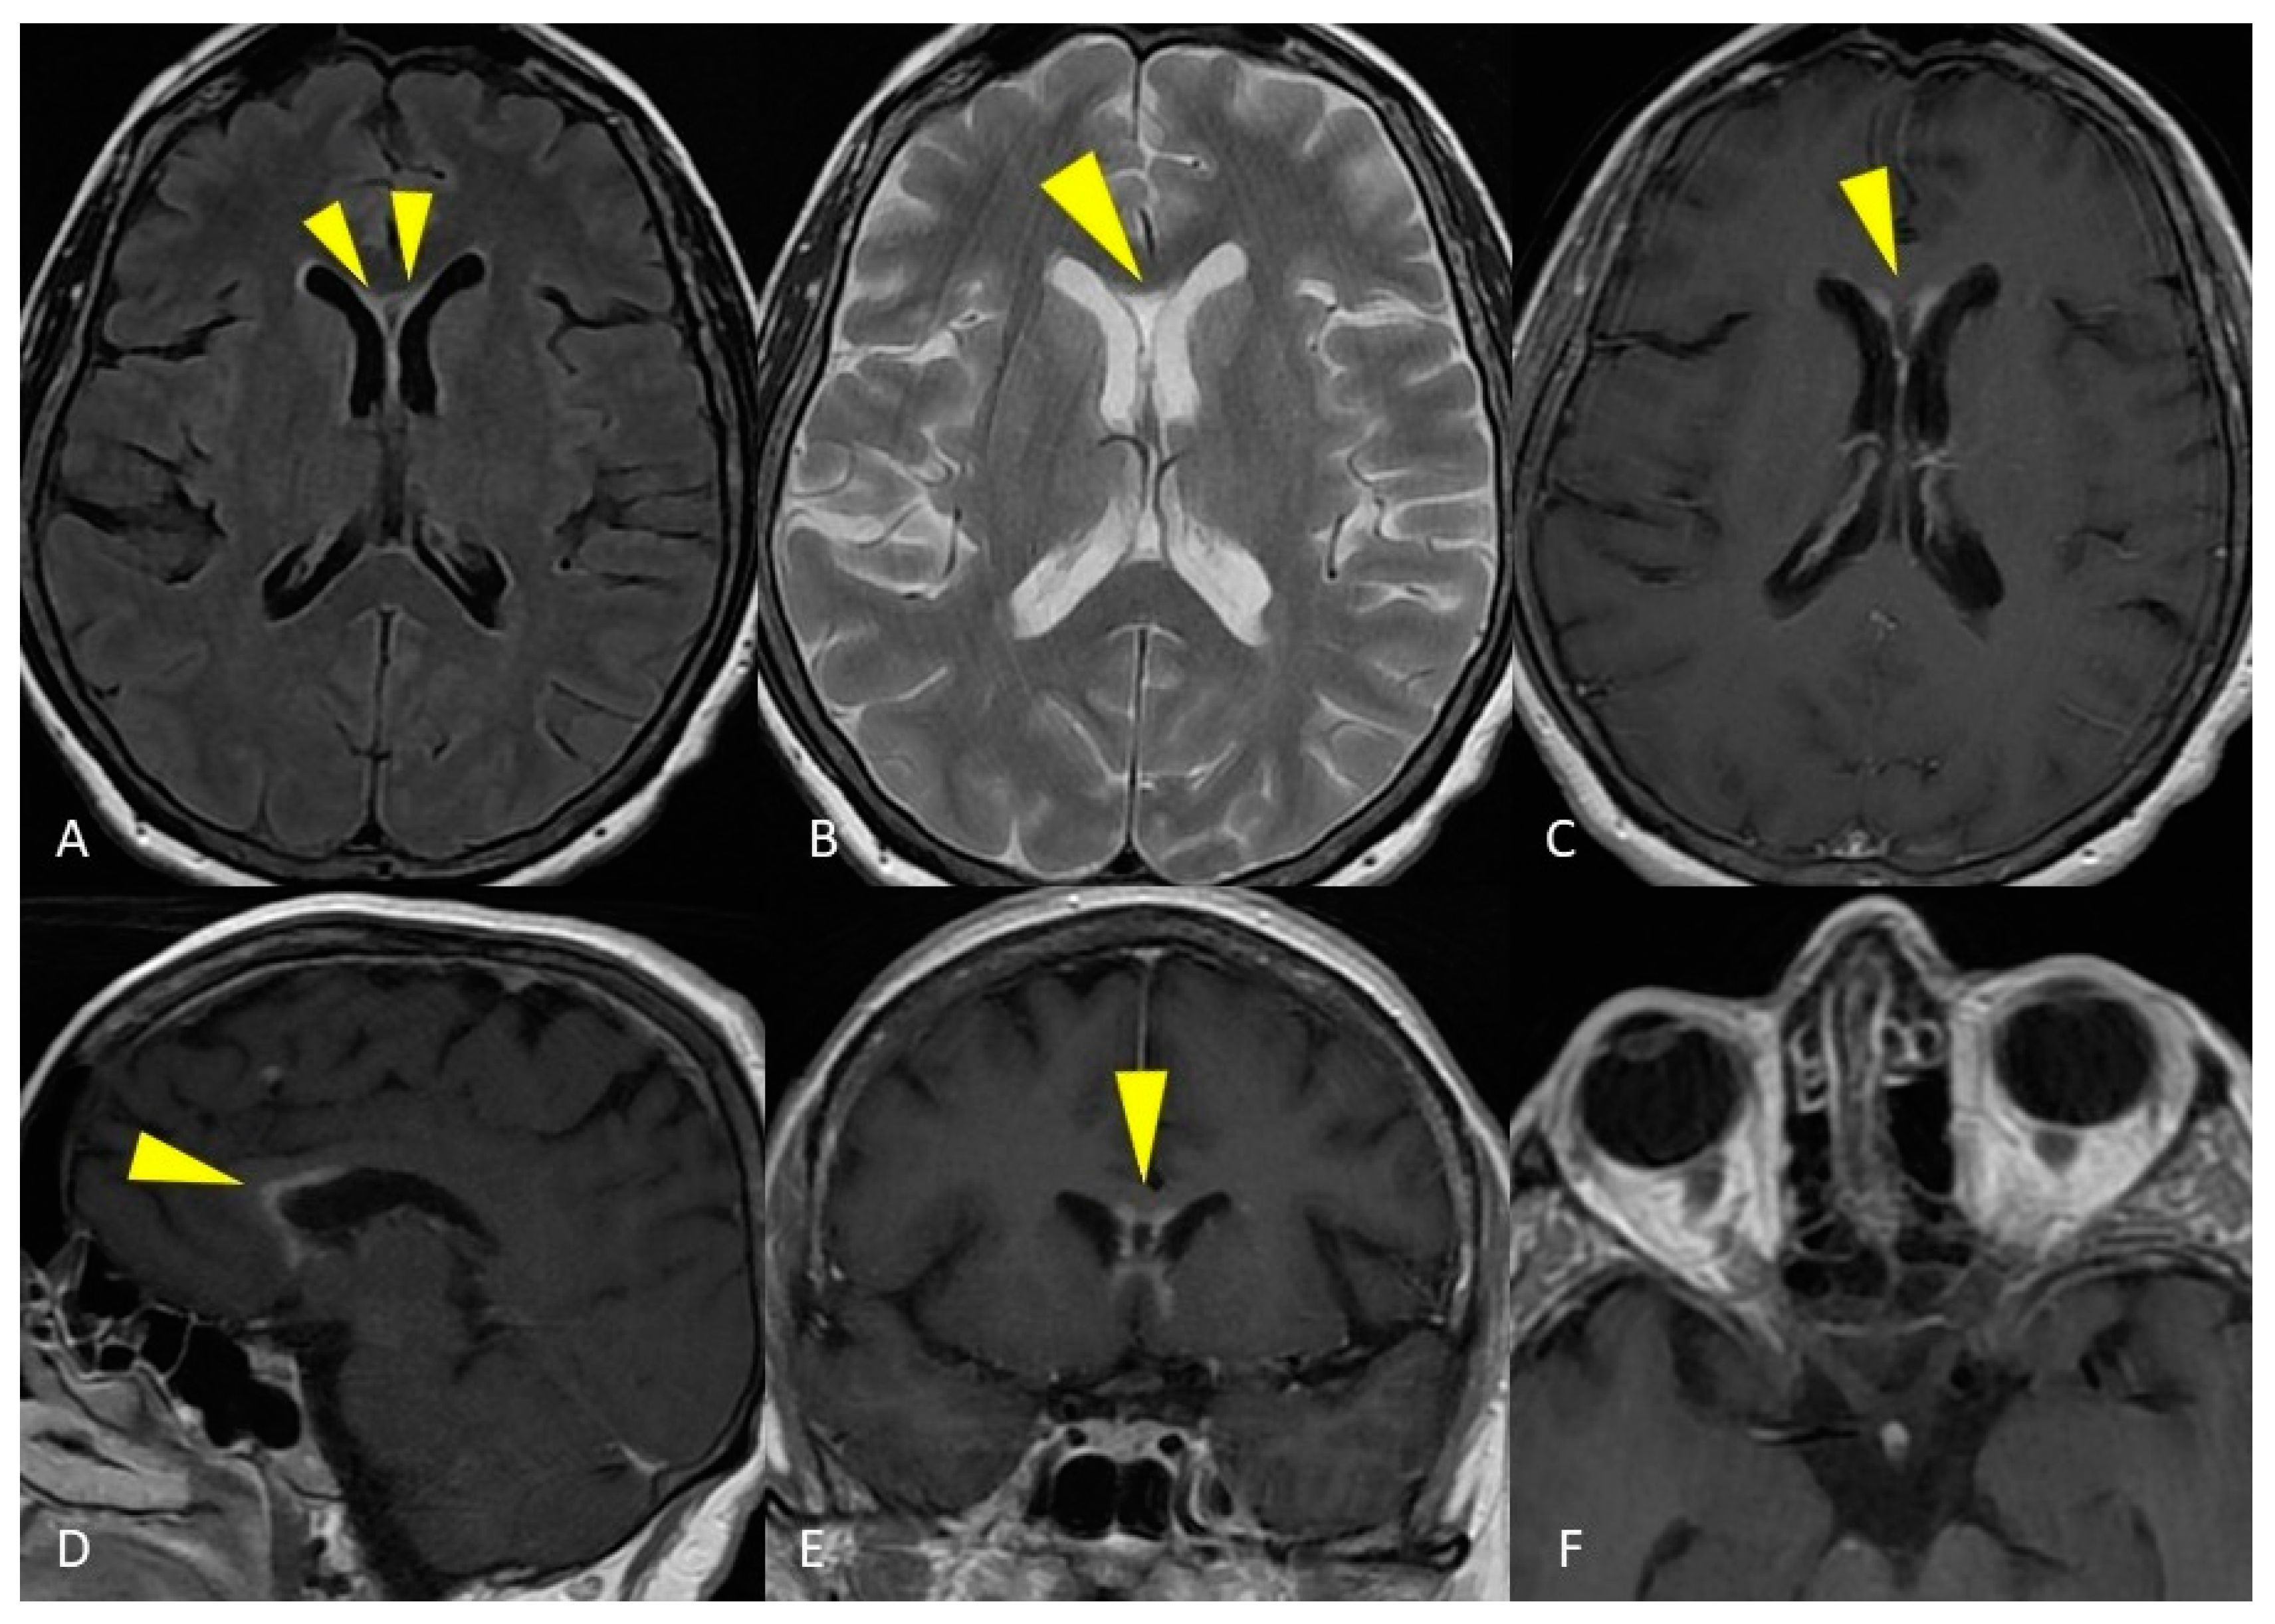

2.2. Case Presentation 2